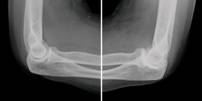

Fig. 9.10 Osteoarthritis. (Sources of images

and videos below. Used with permission.)

Note: (1) the progressive roughening of the round ball and its socket,

(2) the decreasing clear space (cartilage and fluid) between them,

(3) and the extra rough bone (white material) around the joint.

https://commons.wikimedia.org/wiki/File:Severe_(T%C3%B6nnis_grade_3)_osteoarthritis_of_the_hip.jpg

Description English: Projectional radiography of the left hip of

a 65 year old man with pain upon hip movement. It

shows severe (Tönnis grade 3) osteoarthritis.